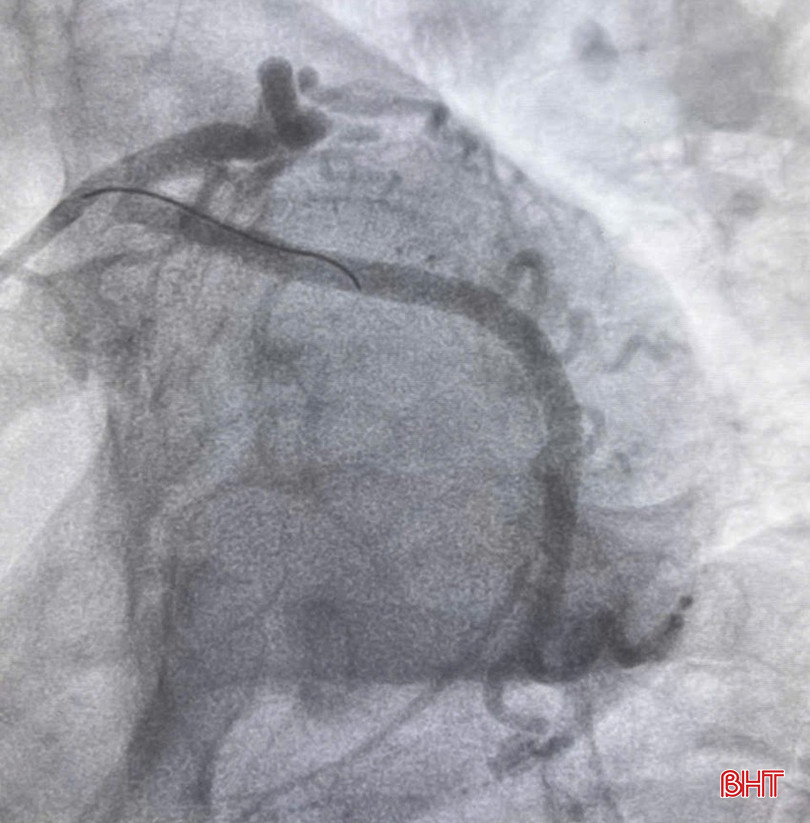

Hình ảnh động mạch vành của bệnh nhân sau đặt stent.

Bác sĩ Khoa Cấp cứu chống độc đã liên hệ hội chẩn Khoa Nội tim mạch, kết luận bệnh nhân bị nhồi máu cơ tim cấp vùng sau dưới và được chụp động mạch vành cấp cứu. Kết quả cho thấy bệnh nhân hẹp khít kèm huyết khối động mạch mũ (1 trong 3 nhánh động mạch vành) nên dẫn tới nhồi máu cơ tim vùng sau dưới. Sau khi đặt stent cho bệnh nhân, động mạch mũ được thông tốt. Sau 4 ngày điều trị, bệnh nhân đã tỉnh táo, huyết động ổn định, tình trạng đau ngực không còn, có thể xuất viện trong vài ngày tới.